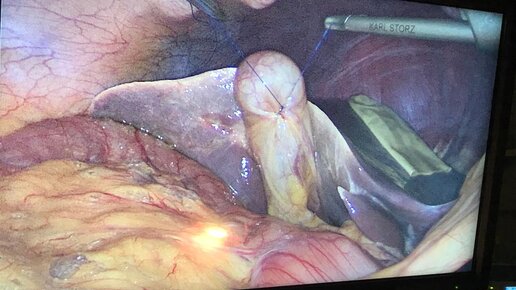

Это диалог при между Дмитрий Ионкинберг и хирургом про операцию по удалению камней из желчного пузыря. Как я удалил полипы из желчного пузыря без удаления самого пузыря, можно сохранить желчный пузырь. - Здравствуйте. Подскажите, пожалуйста, делаете ли вы операцию по удалению пролипов кокрементов из желчного пузыря с сохраненим органа? Консультацию дает врач Шкатов Дмитрий Анатольевич (город Томск) насчет операции по удалению полипов и конкрементов из желчного пузыря с сохранением желчного пузыря...

Все привыкли, что при камнях в желчном может помочь только хирургическое удаление желчного пузыря вместе с камнями – холицестэктомия. Почему 99% врачей выбирают этот путь? Потому что желчнокаменная болезнь не исчезает сама по себе. Если ничего не менять и кардинально не изменить привычки, питание и образ жизни, камни будут формироваться снова и снова. Делать повторную операцию, которая как и любое хирургическое вмешательство, имеет свои риски и нюансы, никто не хочет. Поэтому у врачей «лечение» одно – удаление желчного пузыря...